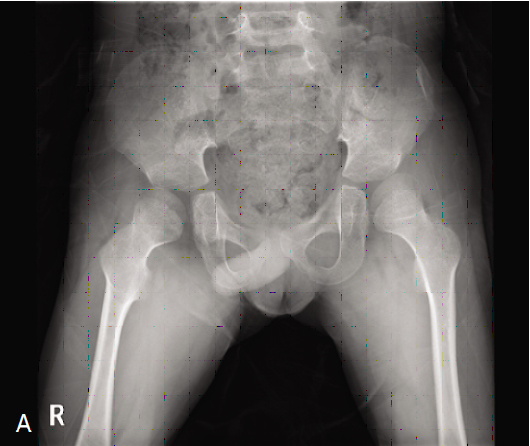

고관절 재건술

뇌성마비 환자에서 고관절 아탈구 및 탈구가 발생하는 경우가 있으며 이로 인하여 통증이 발생하고 앉는자세 유지가 어려우며 청결유지에 문제가 발생할 수 있습니다. 따라서 뇌성마비 환자는 고관절에 대한 정기적인 검진이 필요합니다.

고관절 아탈구나 탈구가 발생한 경우 표준적인 방법으로 관혈적 정복술, 대퇴 내반 감염 절골술, 골반골 절골술을 동시에 시행하게 됩니다.

| 수술 전 |

수술 후 |